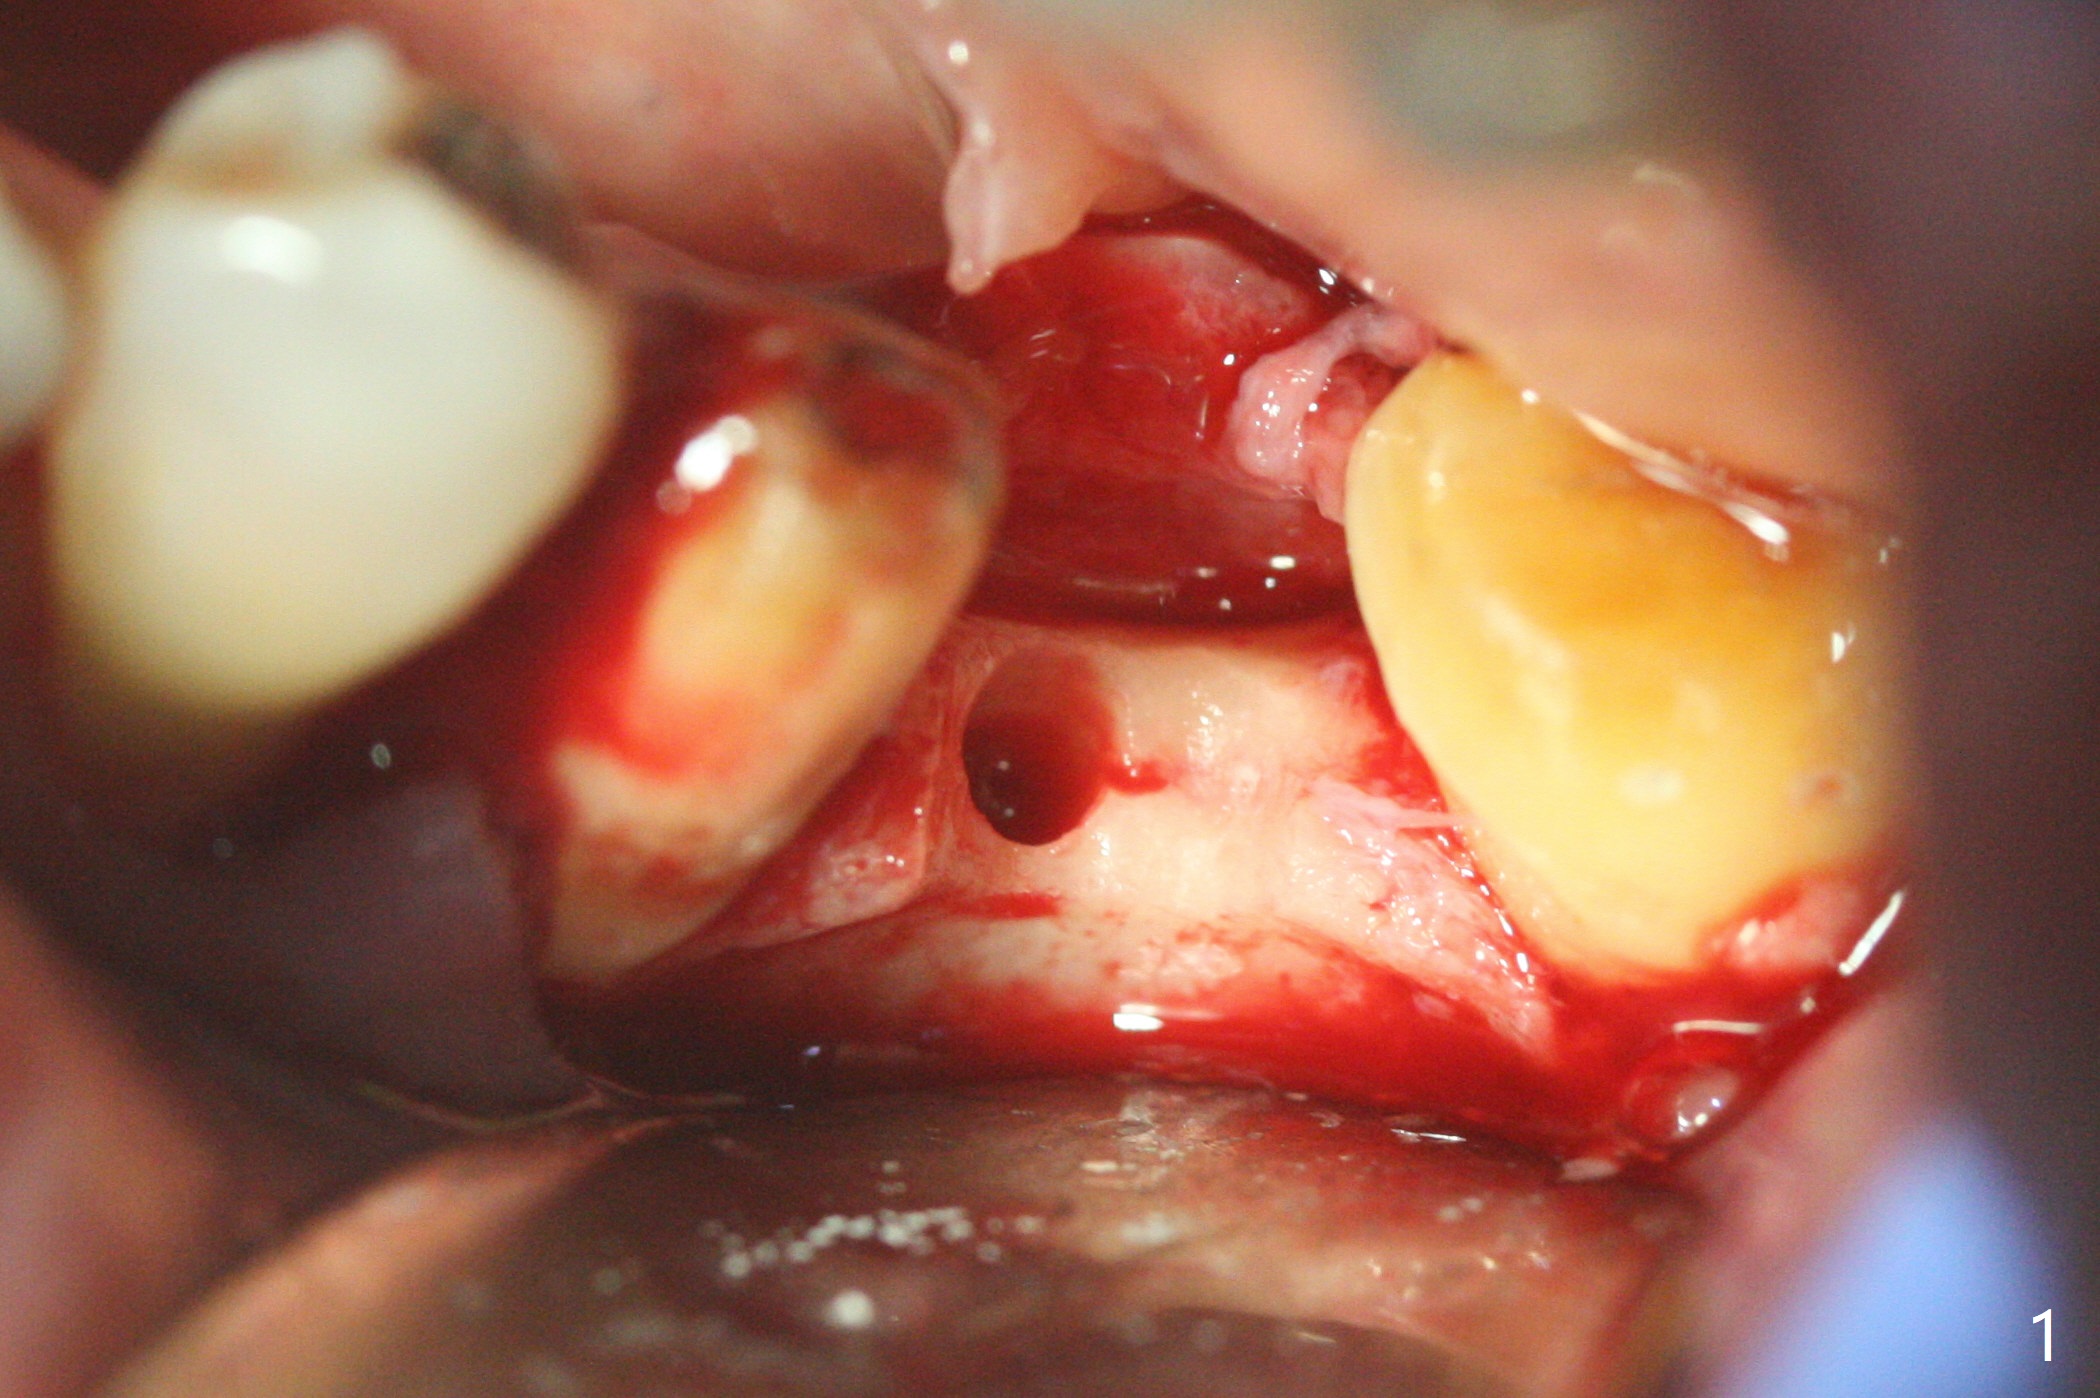

To start osteotomy in the narrow ridge with the oblique top, the latter needs to be trimmed at #19. It would be less traumatic to have a narrow bone trimmer (e.g., 3 mm) in the Narrow Guide Kit. This case is originally designed to have ridge split. The ridge top is trimmed with surgical handpiece after incision. Following pointed drill, the cylindrical part of the 2.2x8.5 mm drill cannot engage to the metal sleeve with 10.5 mm offset. The guide has to be removed. The first 1-2 mm osteotomy has to be done free hand before reuse of the guide and the drill. Nevertheless, the osteotomy is precise buccolingual when it is finished (Fig.1). If the short drill (2.2x7.3 mm) cannot be produced, the next case should have 12 mm offset for narrow guide and an additional guide with regular metal sleeve for tissue punch and bone trimmer. Since the mesiodistal space is also limited, a 2.5x12(4) mm 1-piece implant is placed instead (Fig.2). With the implant placed a little deeper (Fig.3 arrow), bone graft is placed (*), followed by suture. When the procedure is done, the patient is tired. It would be nice to have a more complete Narrow Guide Kit with its own bone trimmer and 2.2x7.3 mm drill. There is no bone loss with retention of bone graft 4 months postop; after reprep of the neighboring teeth, impression is taken (Fig.4). The three crowns are cemented 4.5 months postop (Fig.5).